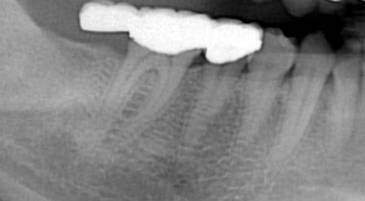

延長ブリッジ

右下 7 番(第二大臼歯)欠損に対してのブリッジです。この患者さんの口腔清掃状態やこのブリッジの前方の歯にほとんど虫歯のないことから、ブリッジの支えとなっている 5 番(第二小臼歯) 6 番(第一大臼歯)もほとんど虫歯が無かったのではないかと考えられます。しかし、 7 番へ歯を入れるためだけに、その神経の生きている歯を大きく削りブリッジにしてあります。